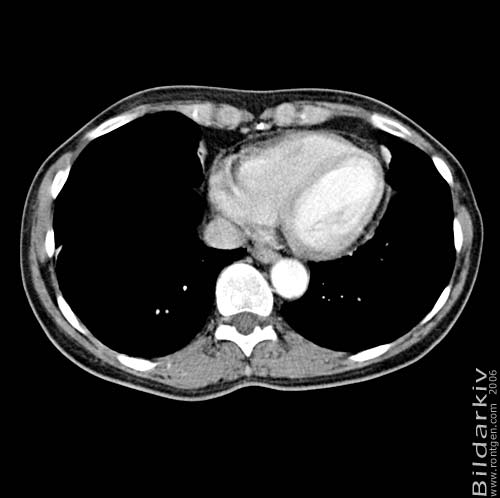

Thorax 44

Snitt över thorax med kontrast. Sk. mediastinum-fönstersättning.

CT Röntgen Helsingborgs lasarett

Mediastinum